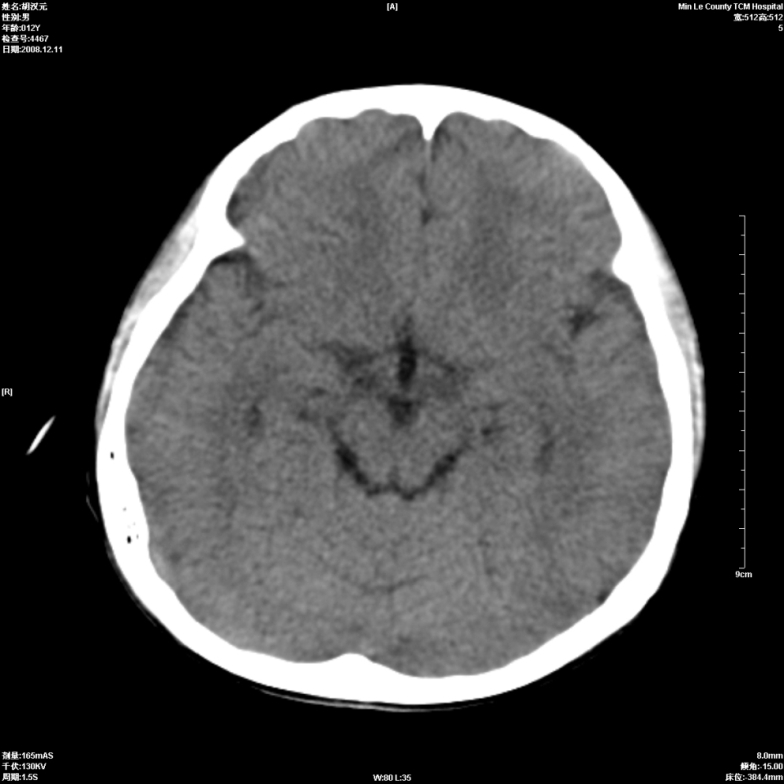

标题: PED1681:头疼发热约一周 [打印本页]

标题: PED1681:头疼发热约一周

颅脑未见确切异常。必要时进一步检查,如mri、脑脊液检查。

两侧顶部近灰质处白质密度降低,是否炎性改变

颅脑ct轴位平扫颅内未见明确异常;建议必要时复查或行进一步检查。

两侧顶部近灰质处白质密度降低,建议mri